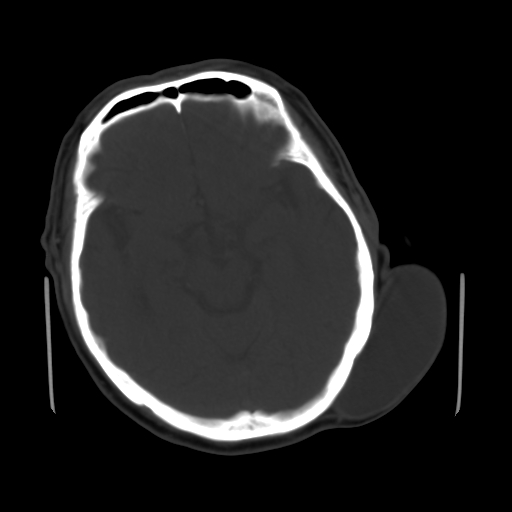

标题: CT25147:男,62岁,右侧肢体活动障碍不灵活三天。 [打印本页]

男,62岁,右侧肢体活动障碍不灵活三天,左侧头皮肿物十余年(ct值8hu)。

1)多发性腔隙性脑梗塞。2)脑白质病。3)脑萎缩。4)左侧枕顶部头皮下皮样囊肿,不排除脂肪瘤。

1)多发性腔隙性脑梗塞。2)脑白质病。3)脑萎缩。4)左侧枕顶部头皮下皮样囊肿或表皮样囊肿。